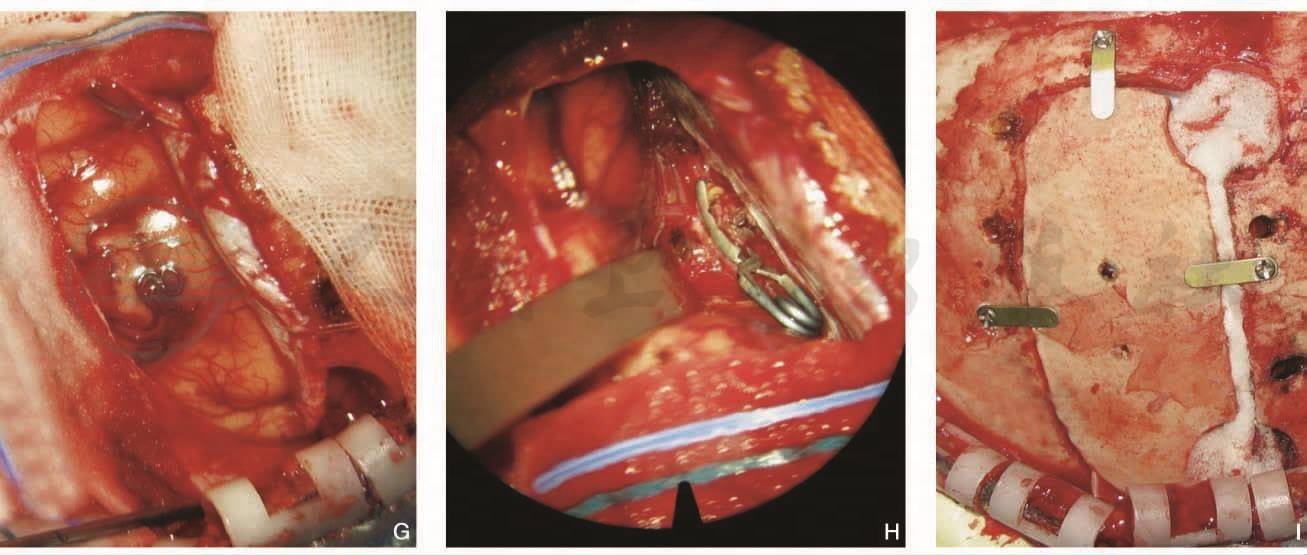

图6女性,64岁,左侧胼周动脉瘤

半球间入路夹闭。手术前左侧颈内动脉造影(DSA)显示胼周动脉瘤(A侧位,B正位),CTA(C)。手术后左侧颈内动脉造影(DSA)显示动脉瘤消失(DE)。左额半球间入路夹闭(FG),夹闭动脉瘤(H)。骨瓣复位固定(I)

引自:血管神经外科学(第2版).第2版.ISBN:978-7-117-37550-4.主编: